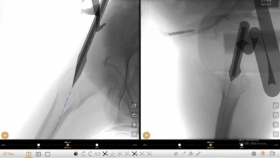

荣昌区人民医院谭响团队斩获省部级科研项目!数智化骨科导航系统开启创伤诊疗新纪元荣昌区人民医院谭响团队斩获省部级科研项目数智化骨科导航系统开启创伤诊疗新纪元近日,重庆市卫生健康委员会公布了2026年科卫联合医学科研项目立项名单。由荣昌区人民医院谭响团队主持...